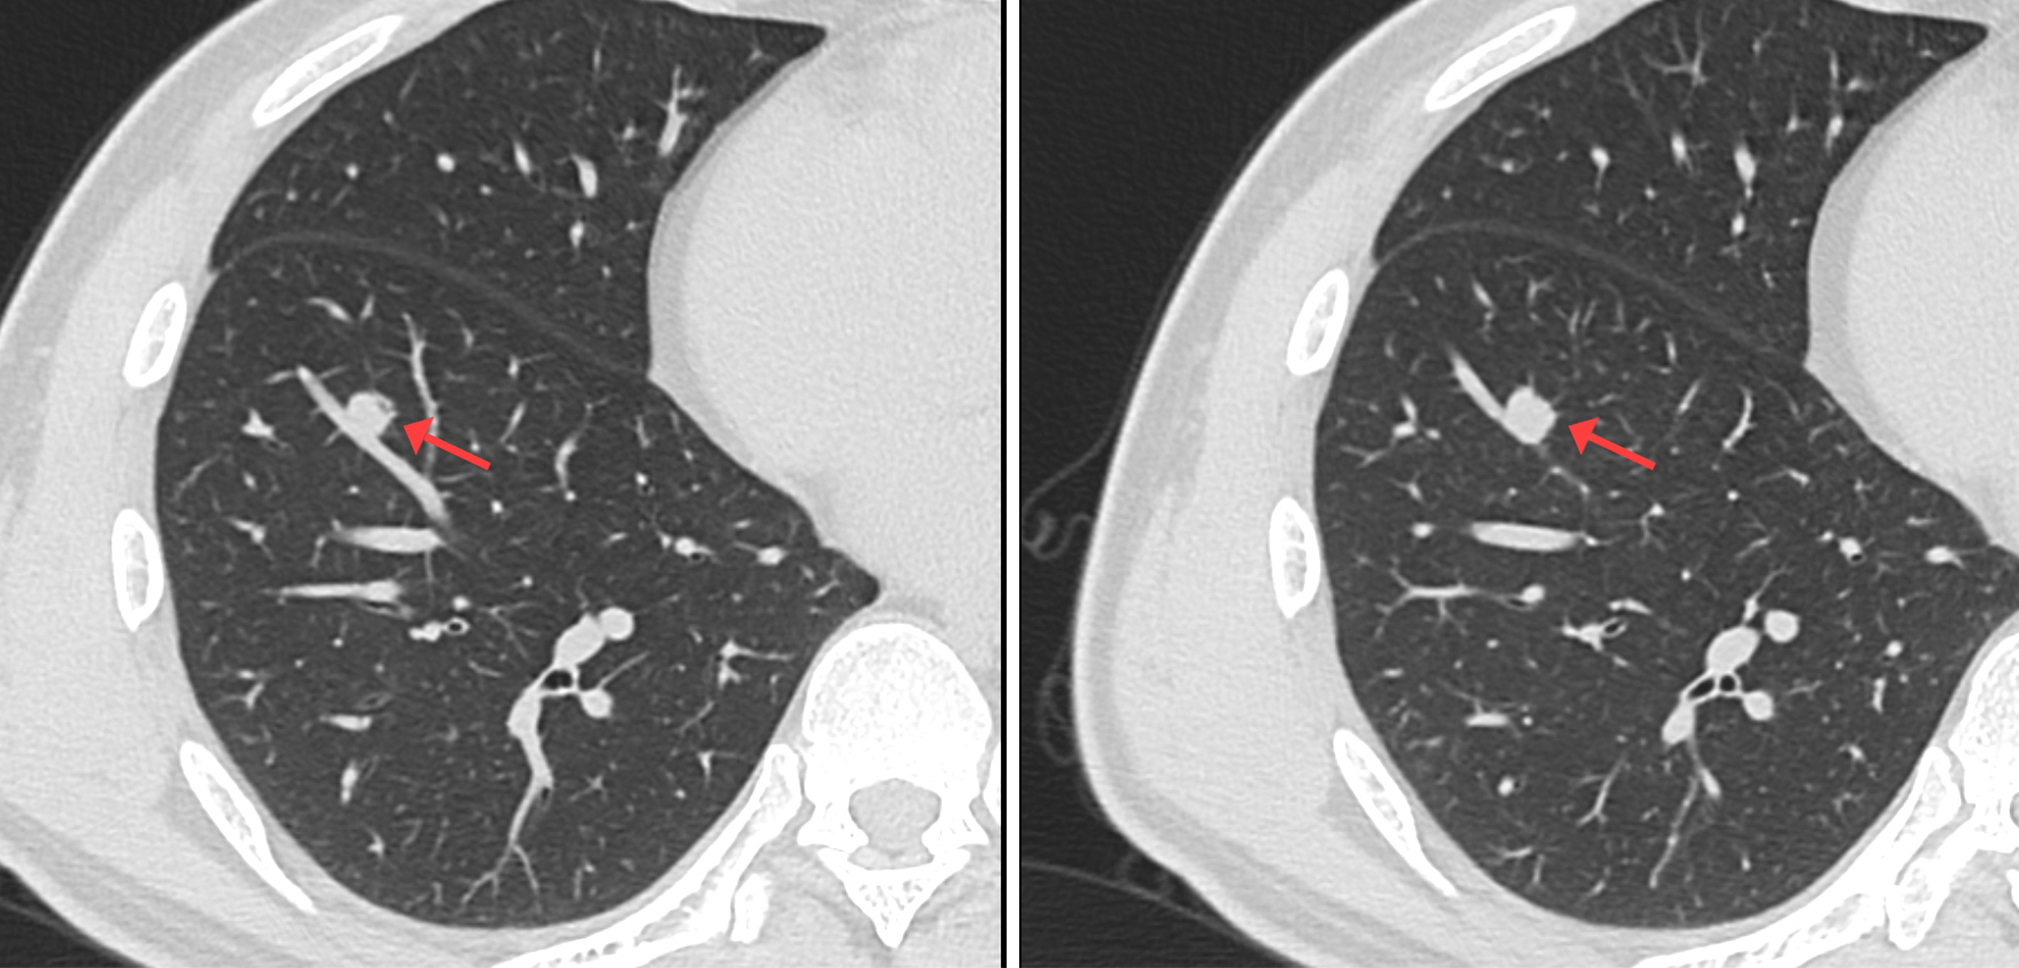

利用小FOV,在相同矩陣狀態(tài)下,視野內像素減小,可以獲取高分辨率的優(yōu)質圖像, 增強了組織間的密度分辨率和空間分辨率,同時可以根據(jù)原始的數(shù)據(jù)來進行后續(xù)重建處理,如:MPR、VR等,可以充分展現(xiàn)出胸膜牽拉征、分葉征、空泡征、毛刺征、支氣管血管集束征等肺癌相關性特征,這是常規(guī)掃描無法比擬的。

中心病例:林先生,吸煙史20年左右。影像診斷:右肺下葉實性結節(jié),考慮腫瘤性病變可能性大,術后證實是肺腺癌。